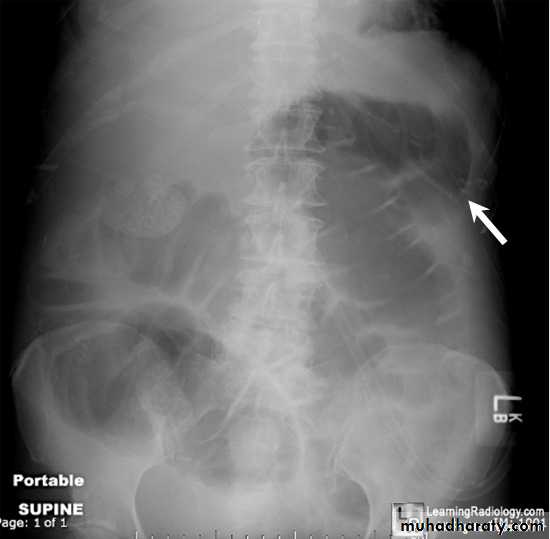

Plain X-ray: abdomen may show sentinel loop, (local ileus).

Colon cut off sign

Sentinel loop

Colon cut off sign• A chest radiograph may show a pleural effusion, and a diffuse alveolar interstitial shadowing may suggest ARDS.